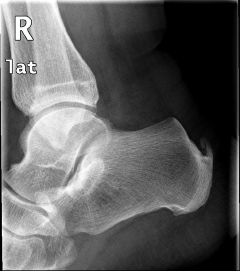

Νόσος Haglund

Πρόκειται για πάθηση που αναπτύσσεται στην κατάφυση του αχιλλείου τένοντα στο πίσω μέρος της πτέρνας. Η περιοχή είναι συνήθως ιδιαίτερα επώδυνη και διογκωμένη λόγω υπερόστωσης (οστικής υπερτροφίας) στην κατάφυση του αχιλλείου. Τα ενοχλήματα μπορεί να συνδυάζονται με πόνο στην περιοχή του πέλματος. Η πάθηση συχνά συνοδεύεται από τενοντίτιδα του αχιλλείου, που καθιστά την θεραπευτική προσέγγιση δυσκολότερη.

Η συχνά εντοπιζόμενη στις ακτινογραφίες «άκανθα» δεν συνδυάζεται κατ’ ανάγκη με την νοσο Haglund.

Προεγχειρητική